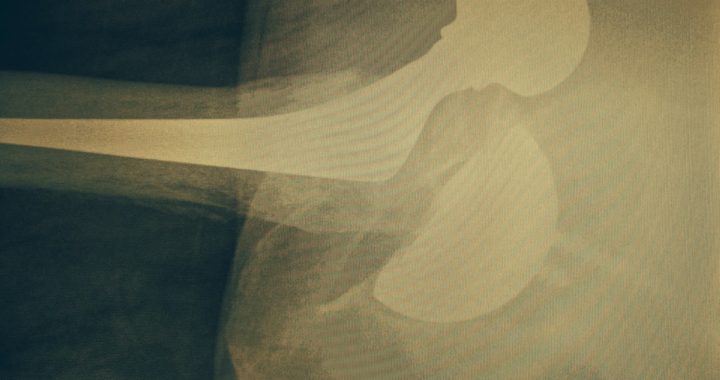

Follow-up after Hip replacement

Once implanted, joint replacements should be periodically followed-up. This follow-up includes taking x-rays to assess the implants. The minimum recommended follow-up for implants with a known good track record involves review at 1 year and thenRead more...